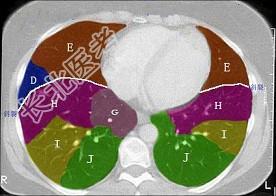

- 单项选择题结合肺段模式(见图),选出右肺下叶的组成 ( )

A、F

B、F+G

C、F+G+H

D、F+G+H+I

E、F+G+H+I+J